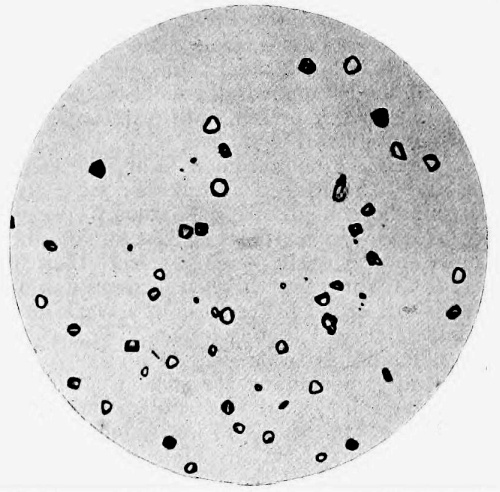

35. Photo-micrograph of Globules of Mercury obtained by Reinsch‘s Process 303

36. Photo-micrograph of Crystals of Hydrochloride of Morphine 339

37. Photo-micrograph of Meconic Acid crystallised from Aqueous Solution 340

38. Photo-micrograph of Meconic Acid crystallised from an Alcoholic Solution 340